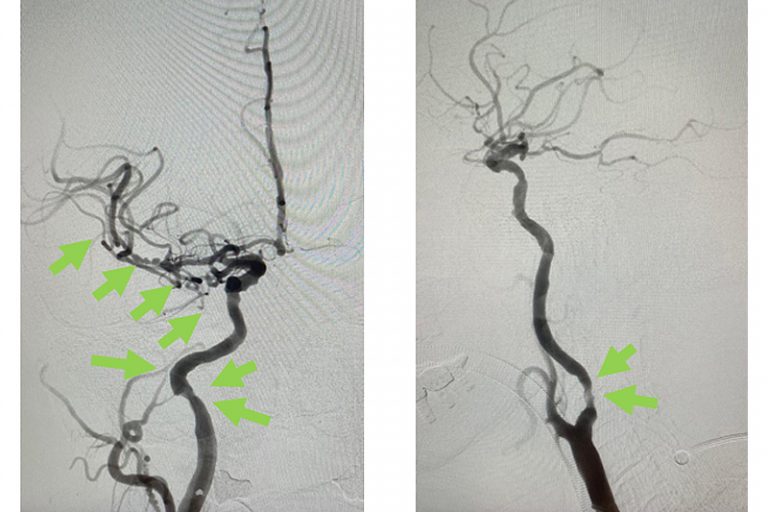

圖:血栓被吸取後, 右頸和腦血管都給順利打通,腦部缺血情況立即得到改善。

經過1小時的血管急救,所有血栓都被移除,羅先生的右頸和腦部血管都給順利打通,腦部缺血情況立即得到改善。血栓被吸取後,腦血管外科醫生發現羅先生的右頸內動脈有嚴重血管狹窄的情況,這個狹窄就是羅先生中風的主要原因。醫生因此植入血管支架來重新擴張狹窄的血管,以防止羅先生將來中風復發。全身麻醉清醒後,羅先生的大腦意識和手腳活動能力即時好轉,他其後再被送回另一間公立醫院繼續康復治療。

圖:血栓被吸取後,發現右頸內動脈血管嚴重狹窄是中風的主要原因。

圖:醫生植入血管支架來重新擴張狹窄的血管,以防止將來中風復發。